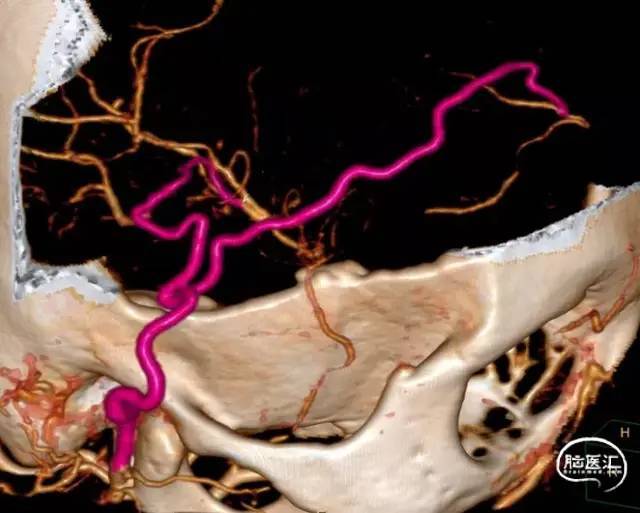

2021年,佟志勇等[17]回顾了2019-2020年5例STA-MCA/ACA序贯双吻合术(SDA)治疗MMD的病例,其中3例为STA-MCA-STA-ACA序贯双吻合术(世界首例)。STA中段和M4侧侧吻合,STA末端的额上回A5端侧吻合。使用单定点连续缝合法。术中测量STA压强为74mmHg(1mmHg=0.133kPa),A5压强为28mmHg,M4压强为29mmHg,STA侧壁压强为65mmHg。术中STA的切割流量(CF)为15~36ml/min,平均(23.6±7.7ml/min;术后1周STA流量为40~125ml/min,平均(96.8±31.2)ml/min。术后1周STA血流量为术中CF的4.1倍。

2021年,余冠东和佟志勇等[18]回顾对照研究了STA-ACA和STA-MCA双吻合术(DBA)与STA-MCA双吻合术治疗MMD的疗效。纳入2017-2020年的32例ACA供血区缺血的MMD患者共计41例次手术,分别行STA-ACA和STA-MCA双吻合术联合EMS(ACA组,10例计10例次手术)(2019-2020年)和STA-MCA双吻合术联合EMS(MCA组,25例计31例次手术)。结果显示:ACA组治疗ACA供血区缺血的MMD,桥血管通畅性良好,可获得满意的长期疗效;与MCA组相比,ACA组STA的切割流量指数(CFI)值更高,而两组术后长期疗效相当。

综上所述,MMD的ACA直接重建术出现于1981年[5],以纵裂内的胼周动脉或胼缘动脉为受体动脉,移植胃网膜动脉或头静脉,属于第二代脑血管重建技术。1997年[13]出现了以额上回A5为受体动脉的ACA直接重建术。2019年[17]出现了STA-MCA-STA-ACA序贯双吻合术。目前的ACA重建术均把A5作为受体动脉,STA-ACA端侧吻合。当STA长度不足时,可以间置STA(长度小于4cm)。

佟志勇等自2019年1月[17,18]开始挑选STA长度理想、ACA供血区缺血的烟雾病患者行STA⁃ACA吻合术。该术式的核心为: